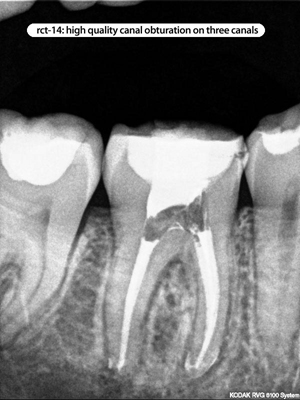

Root Canal Cases